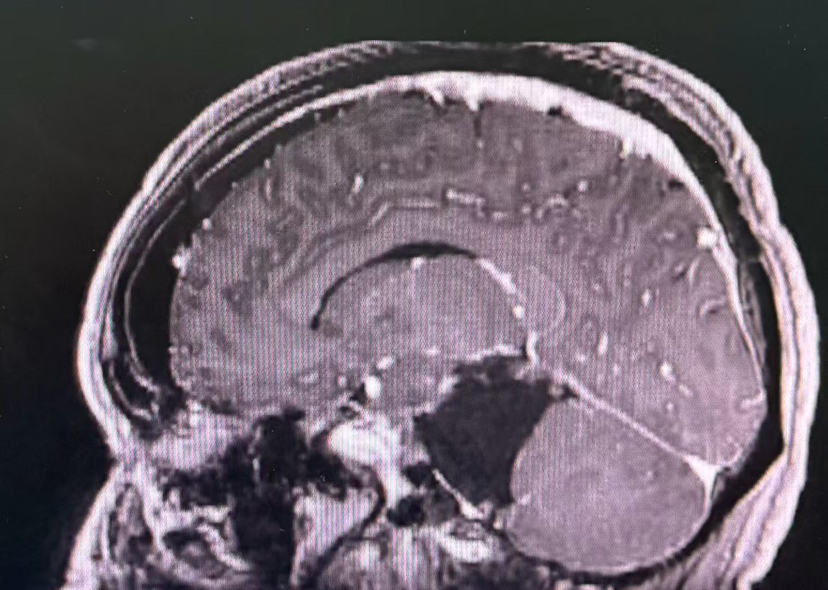

术前MRI

术后MRI